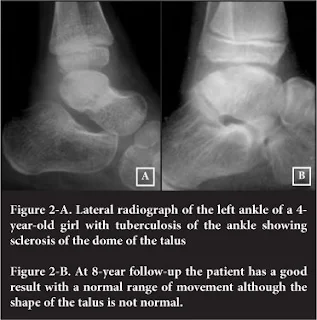

X-ray of Ankle Joint- Regional Osteoporosis

Bone abscess

Narrowing and irregularity of joint space